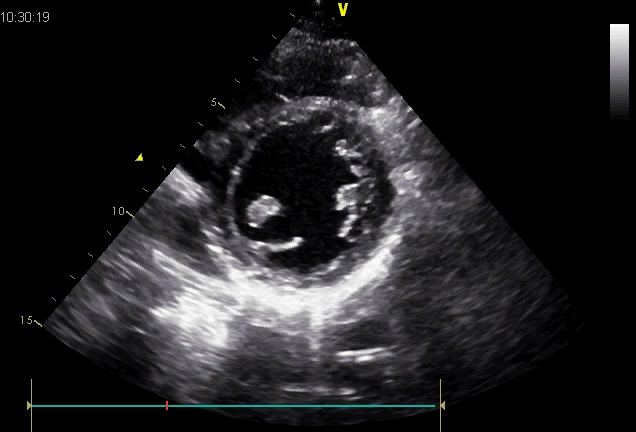

心梗后:左室下后壁的室壁瘤

乳头肌短轴观

二尖瓣短轴观,瓣叶是否有些厚?